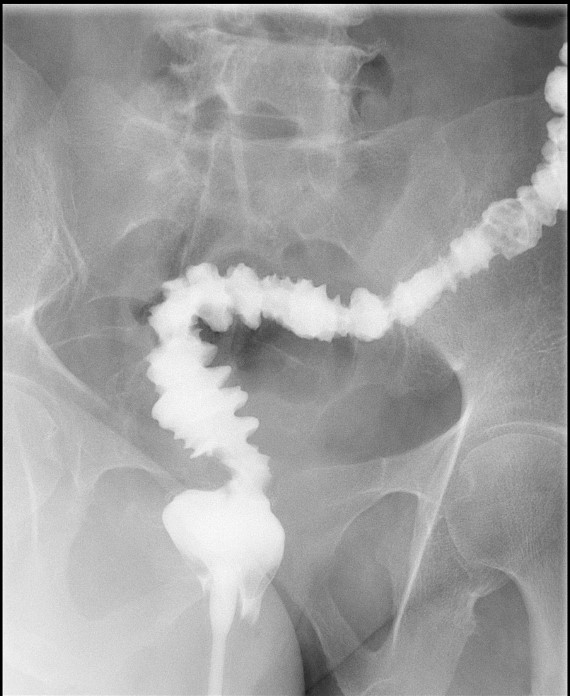

- Method:

- Verify NPO status.

- The technologist will obtain a scout image. Assess the image for any possible contraindications such as pneumoperitoneum, evidence of ileus or obstruction, or residual contrast material

(key image 1).

- If no contraindication, let the technologist know it is okay to proceed.

- The patient will be given a cup of thin barium.

- Once 15 minutes has passed since the patient drank the barium, the technologist will obtain a prone (if possible) radiograph

(key image 2).

- Prone positioning is preferred because while lying prone, the weight of the body provides compression of the bowel loops.

- The film should include the entire stomach as well as the bowel that is filled with contrast.

- You will now be waiting for barium to reach the large bowel.

- The technologist will obtain radiographs at 30, 45, and 60 minutes after the initial administration of barium. If the column of contrast material has not reached the large bowel on the 60 minute film, the technologist will obtain images every 30 minutes until contrast can been seen in the cecum

(key image 3)

(key image 4)

(key image 5).

- Once the barium has reached the small bowel, you will go into the room and obtain spot images of the contrast material filled small bowel.

- Obtain images of the terminal ileum and the ileocecal valve filled with contrast material

(key image 6)

(key image 7)

(key image 8)

(key image 9)

(key image 10).

- Obtain spot images of the remainder of the small bowel

(key image 11)

(key image 12)

(key image 13)

(key image 14).

- Obtain images of all four quadrants. Use the compression paddle to separate loops of small bowel from each other.

- Evaluate for tethering of small bowel to any other structures.

- Observe for small bowel peristalsis.